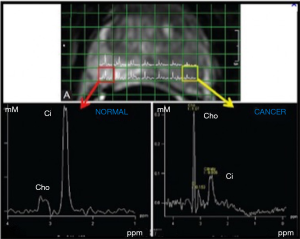

Spectra were analysed on voxels located within healthy prostate and cancer, and specifically indicated by the radiologists on T2w images. LC Model software was used to quantify Citrate (Cit), Choline (Cho) and Creatine (Cre) resonances with respect to water to yield the corresponding pseudo-absolute metabolite concentrations (expressed as mM) cCit, cCho and cCre (Figure 2).